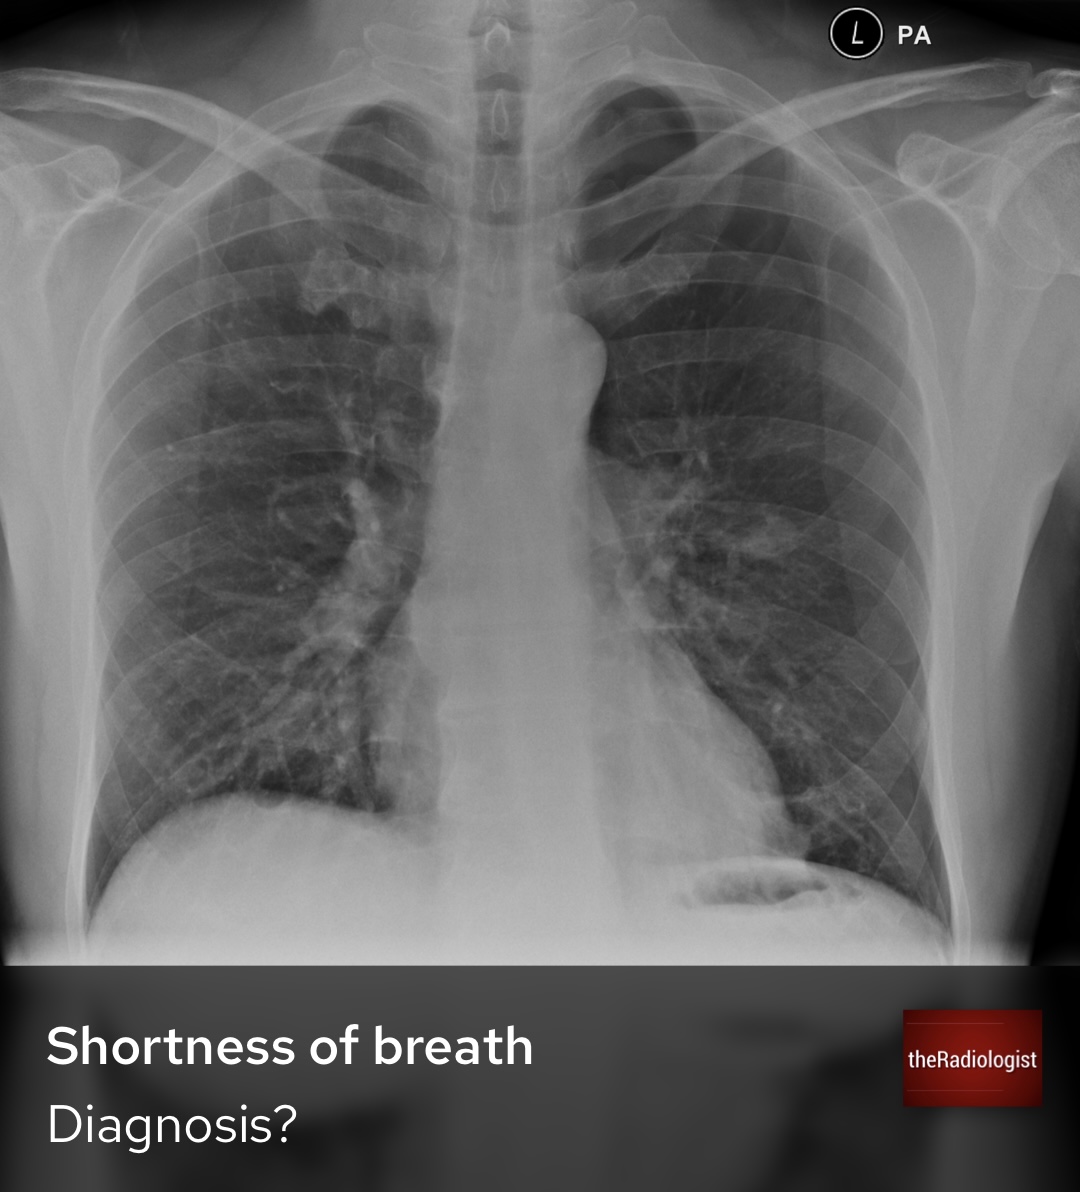

What is the most pressing abnormality on this X-Ray? Open thread for the explanation.